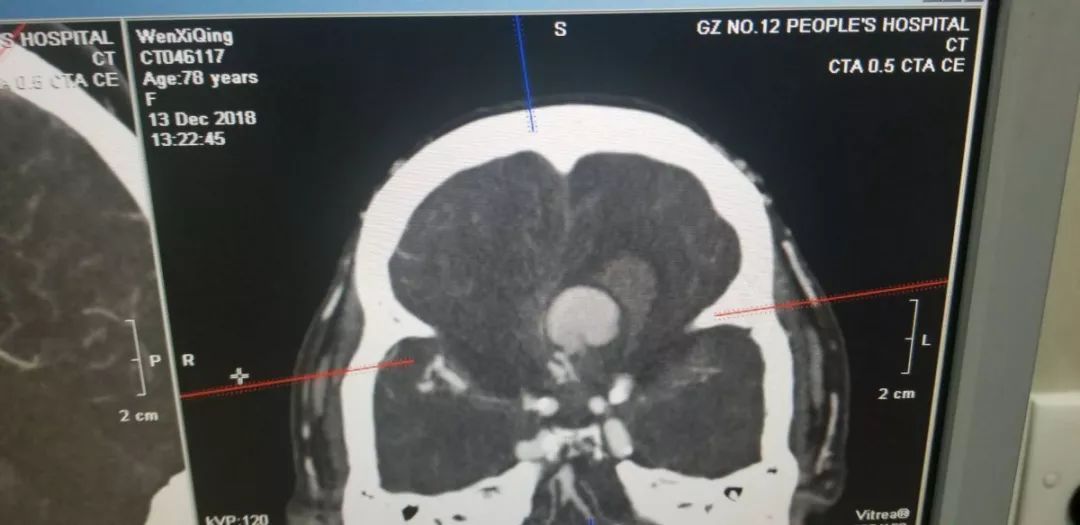

在多科医生、护士的严密监护下,完成了CTA检查,果然发现胼周动脉瘤。

该患者Hunt-Hess分级为五级,预后不良,一般不建议手术,但家属坚决要求积极手术抢救,考虑到患者瞳孔散大时间不长及家属的强烈意愿,当机立断放手一搏,患者迅速被推入手术室,在动脉瘤已经破裂的情况下,争分夺秒赢得了宝贵的手术时间。